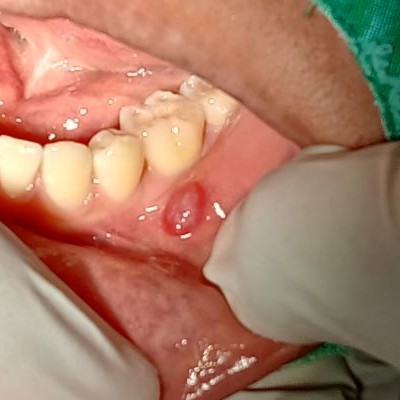

혀의 섬유종 제거 N새글 혀의 섬유종 제거입니다. 구강외과 전문의가 수술합니다. -----------------------------..

혀의 섬유종 제거 N새글 혀의 섬유종 제거입니다. 구강외과 전문의가 수술합니다. -------------------------------..

혀의 섬유종 제거 혀의 섬유종 제거입니다. 구강외과 전문의가 수술합니다.